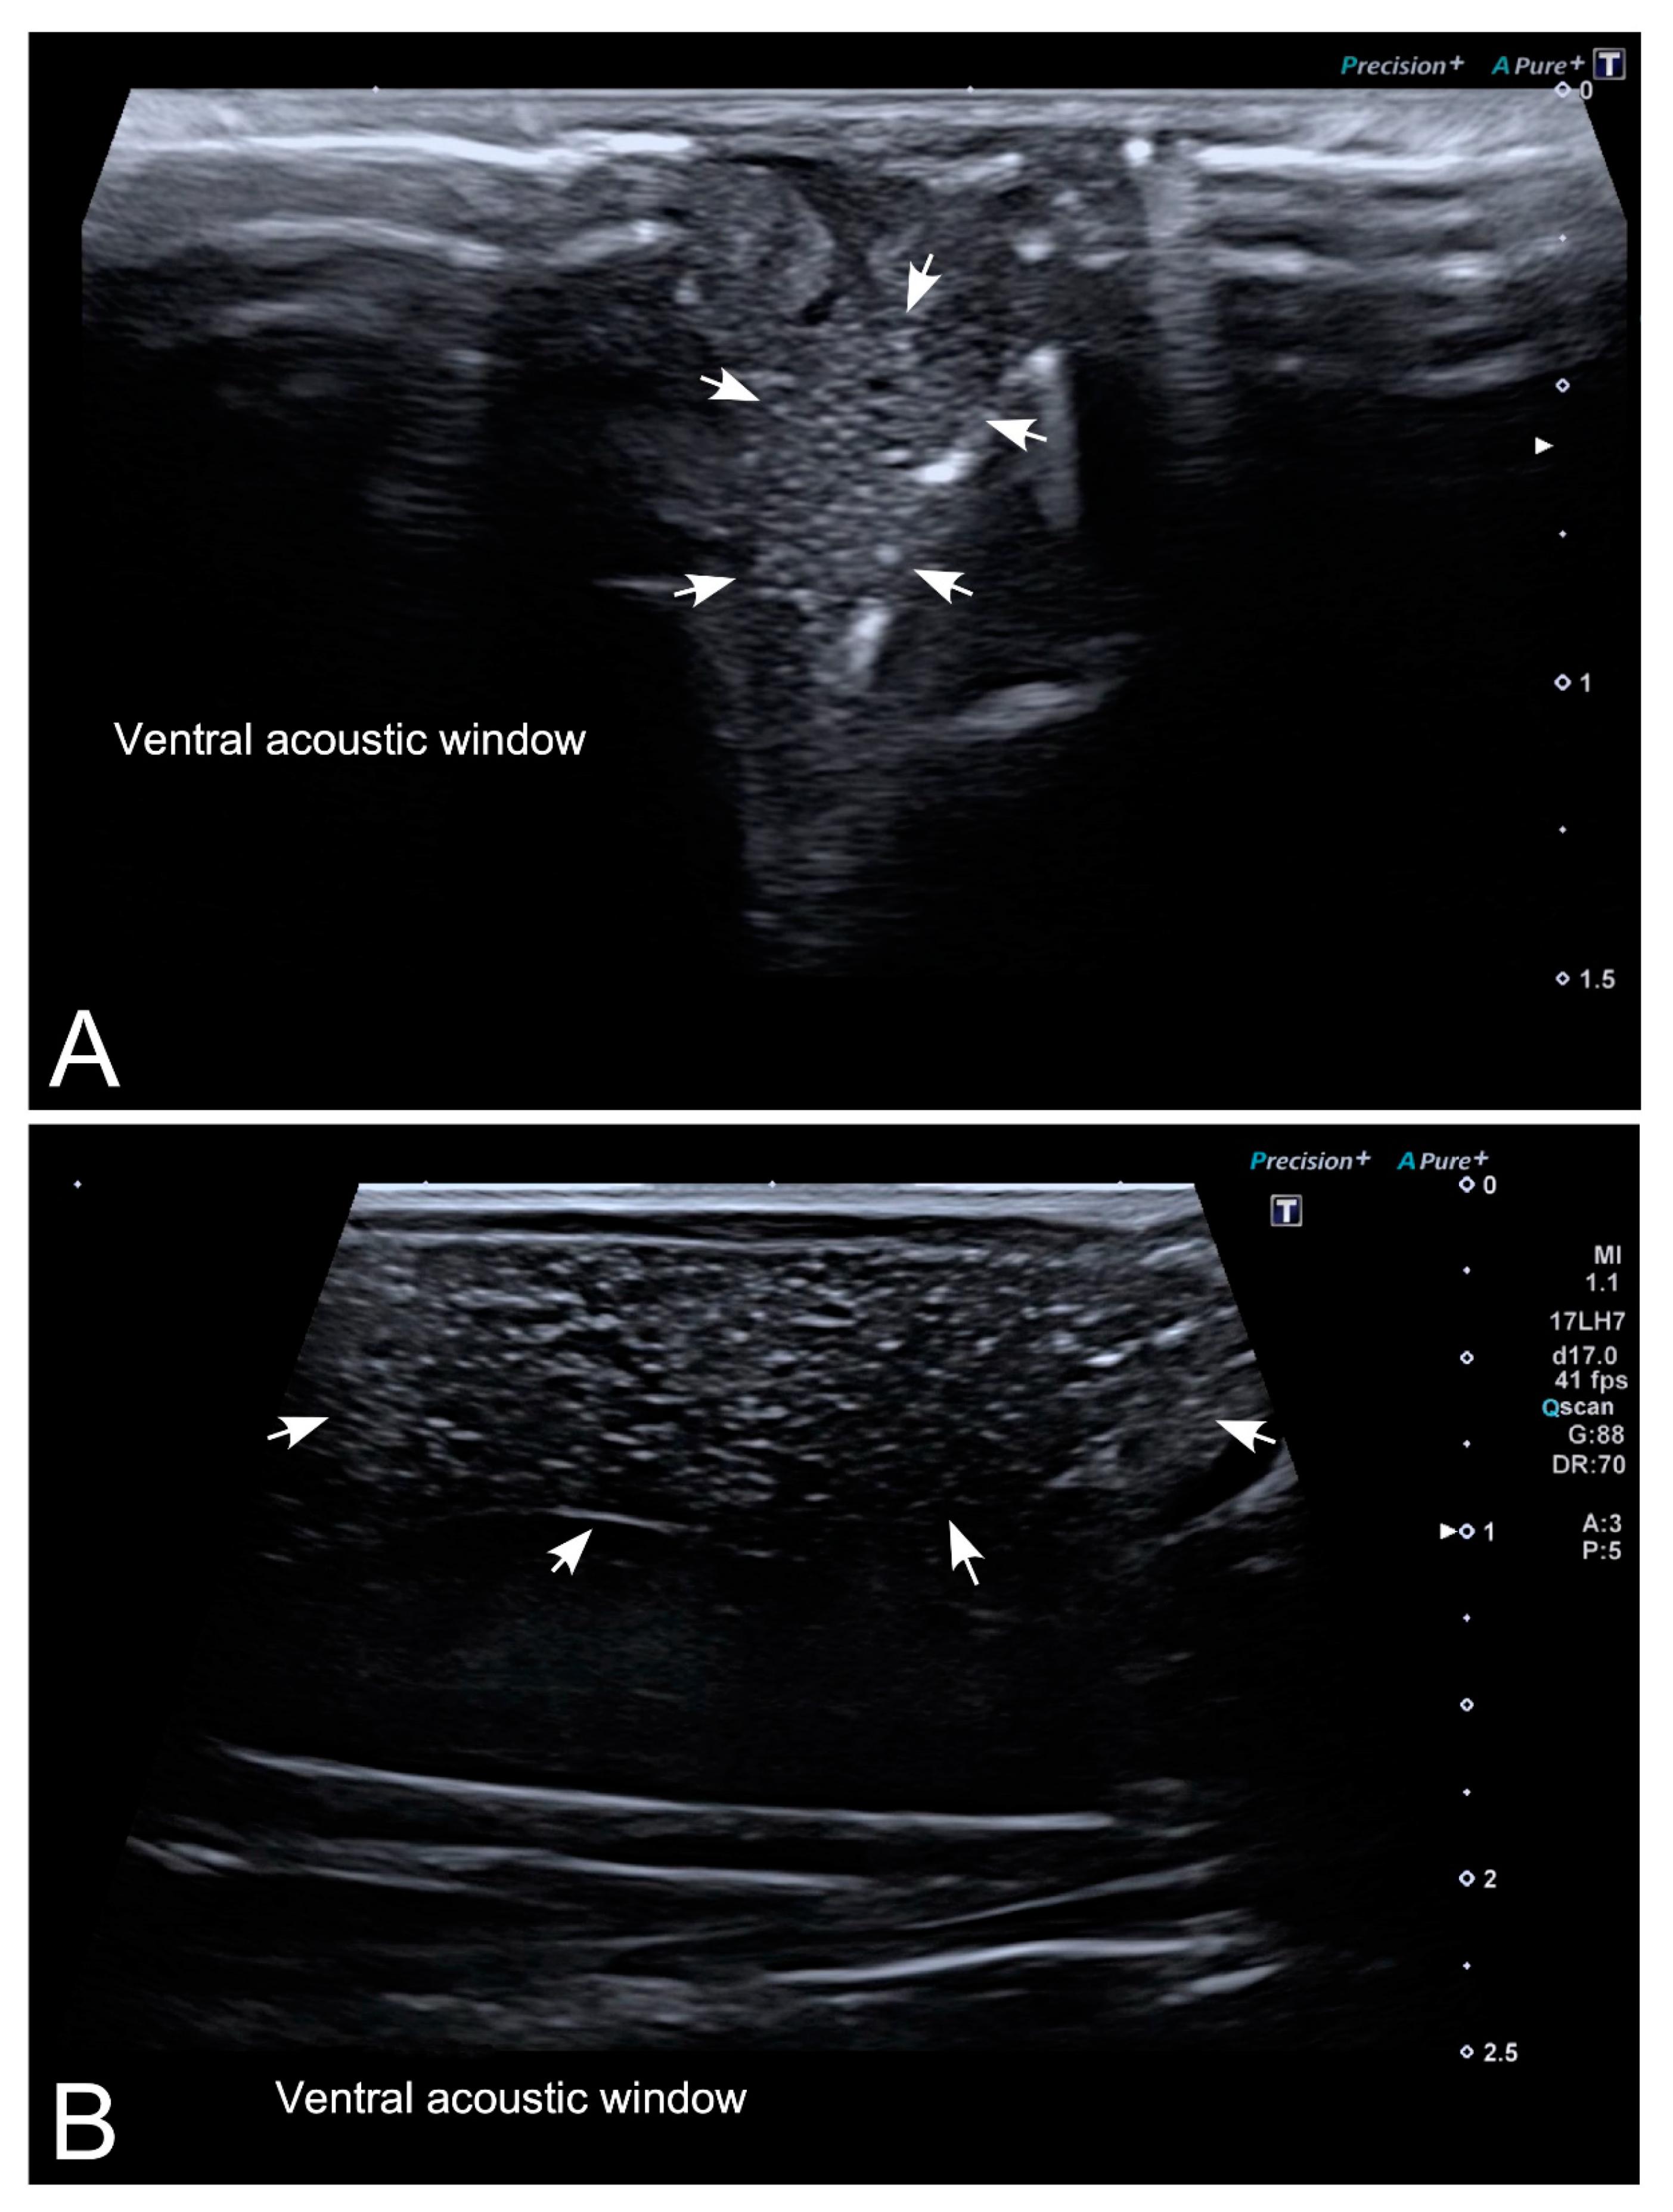

Figure 4. Representative high-resolution ultrasound (HR-US) images of a female Kaloula pulchra obtained in the transverse plane (A) and a female Xenopus laevis (B) obtained in the longitudinal plane using, in both cases, a ventral acoustic window. Follicles appeared as a complex of anechoic or hypoechoic rounded or oval areas separated by hyperechoic lines.